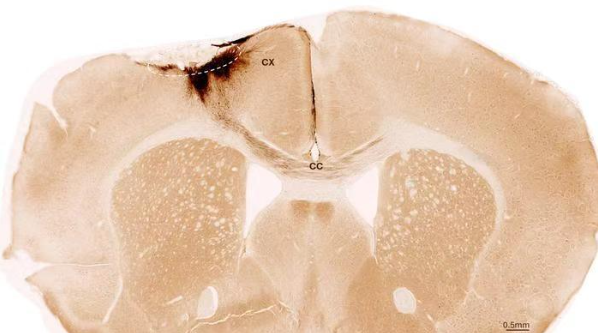

神经干细胞移植后小鼠大脑的冠状切面。虚线圆圈标示了中风区域。移植的人类细胞所发出的神经突起被染成深棕色。这些神经突起不仅向局部皮层(CX)延伸,还通过胼胝体(CC)延伸至另一侧大脑半球。图片来源:苏黎世大学